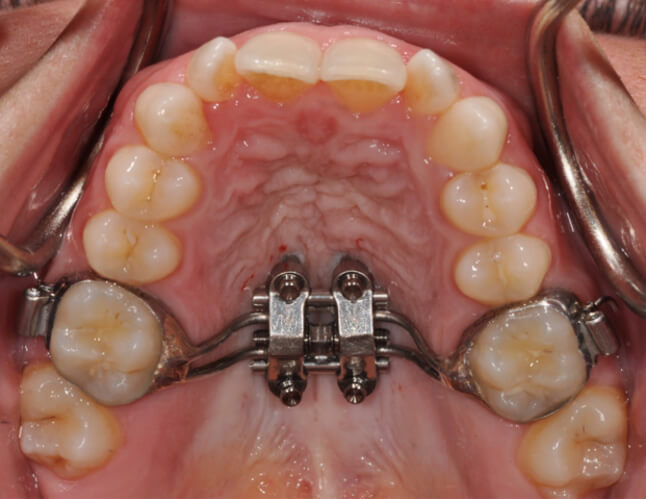

CUSTOM MARPE FOR MATURE PATIENTS

For teens and adults with underdeveloped upper jaws or airway concerns, Dr. Bockow offers custom MARPE (Miniscrew-Assisted Rapid Palatal Expansion). Unlike traditional expanders, MARPE uses precise digital planning and bone-anchored expansion to achieve results even after growth is complete.

Each MARPE is customized to the patient’s anatomy for maximum comfort and effectiveness. Because of this expertise, patients frequently travel from across the country for Dr. Bockow’s specialized treatment.